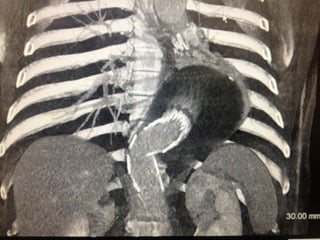

• Preoperative CT 1mm imaging to include pelvisPreoperative CT 1mm imaging to include pelvis